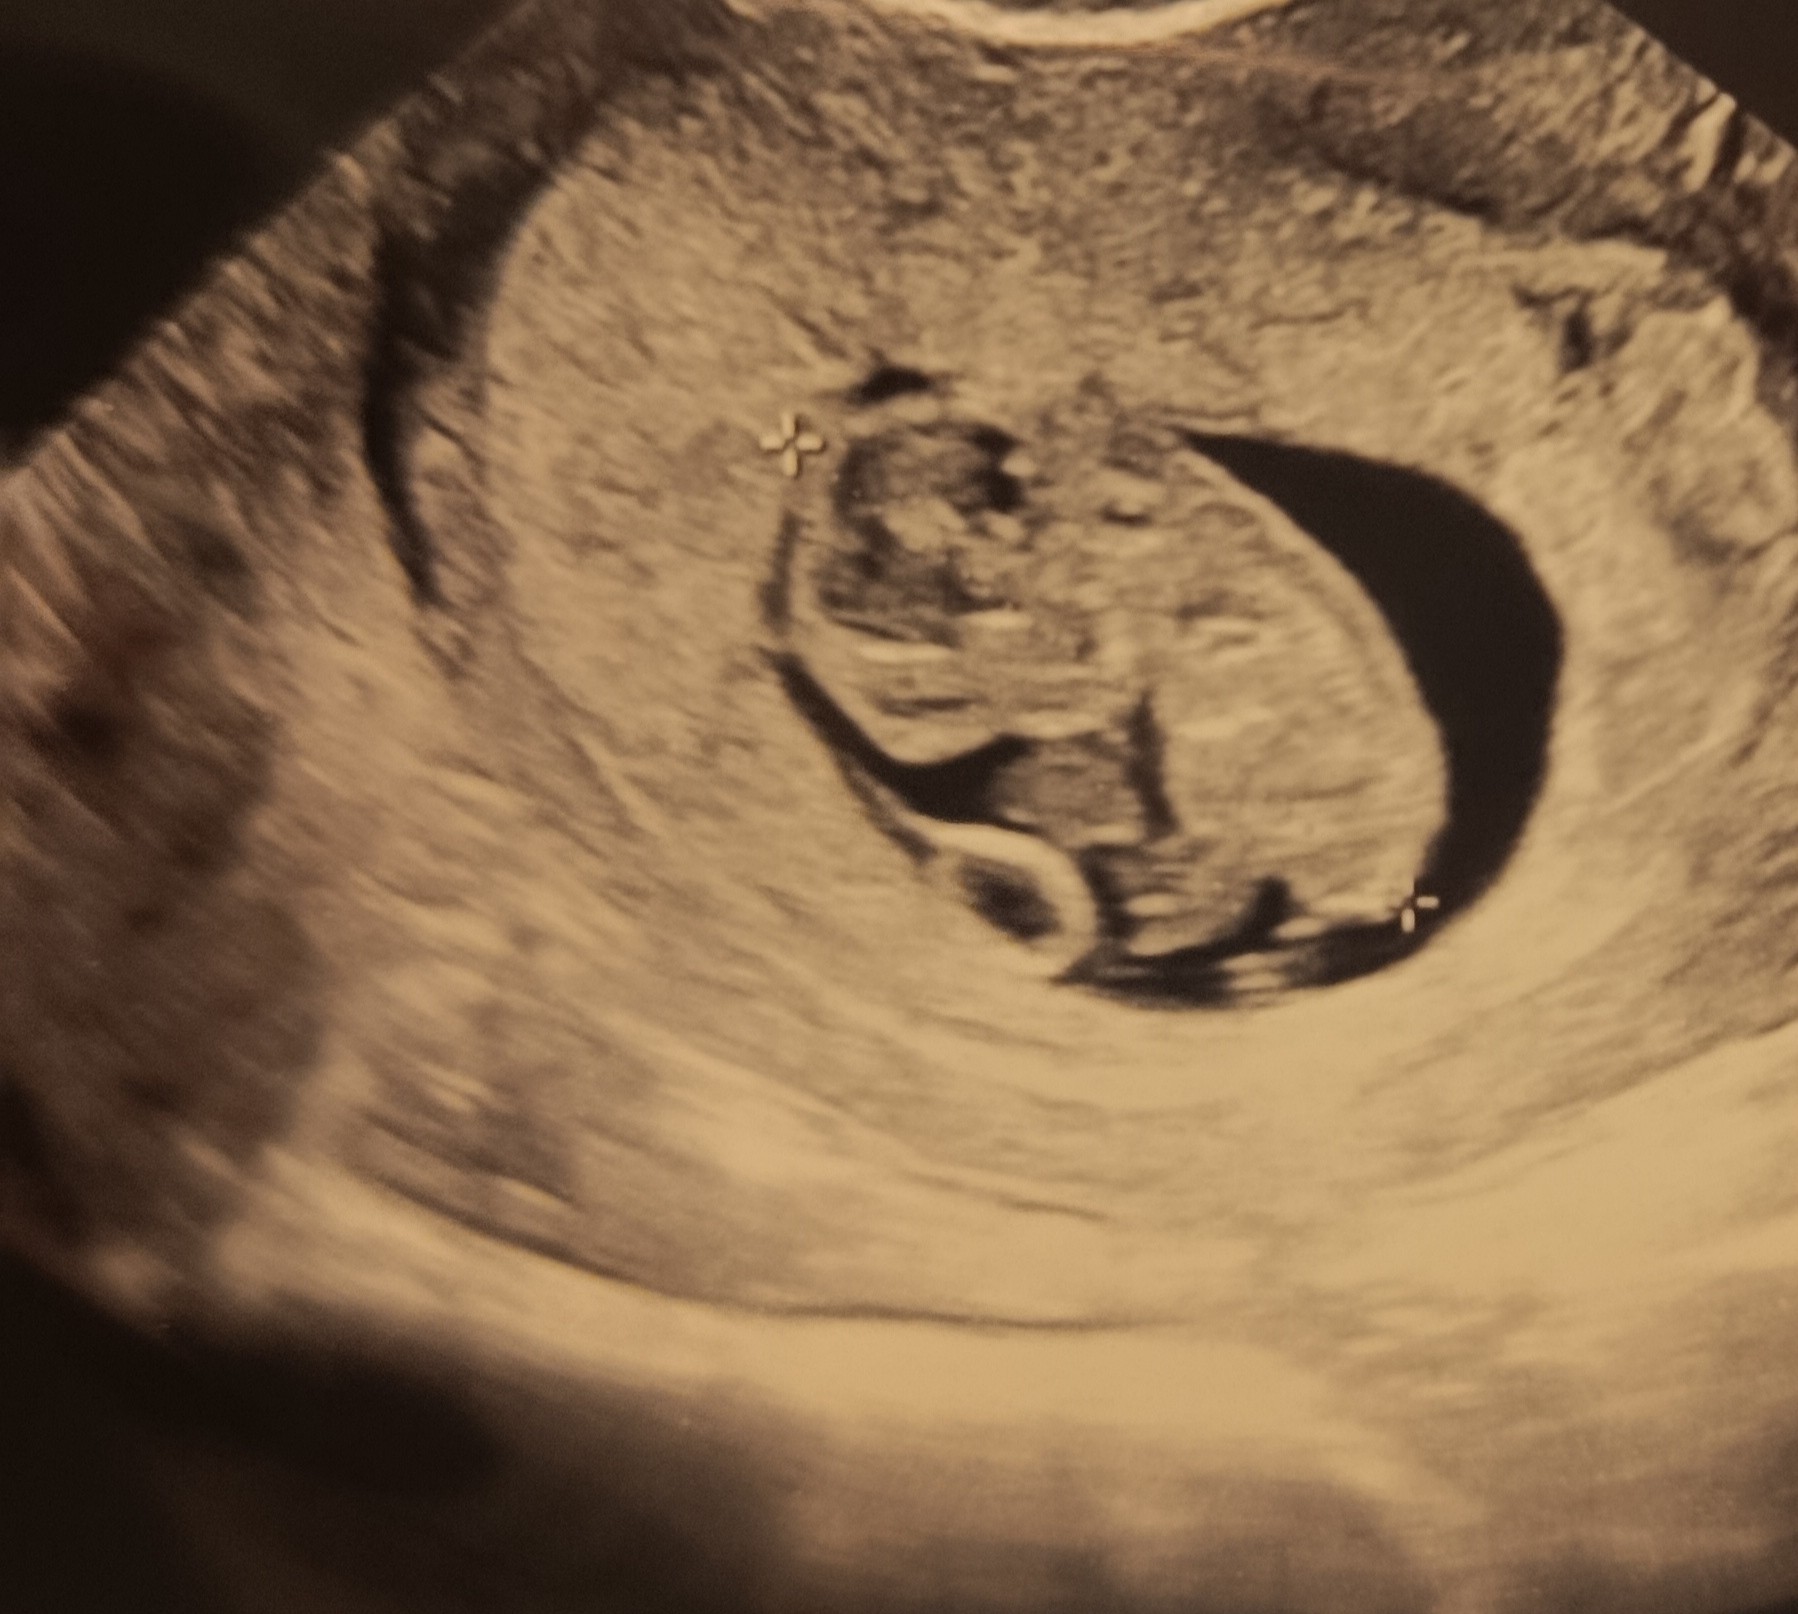

A to mój mały ludek 🥹 wszytsko pięknie, książkowo, ma 2,5cm, serce bije 182. Ruszał się na tym usg już, jakie to piękne

Zobacz załącznik 1730367